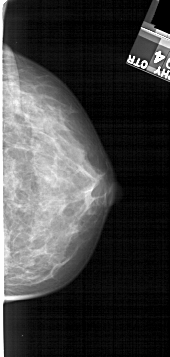

A_1272_1.RIGHT_CC

RIGHT_CC LINES 4996 PIXELS_PER_LINE 2371 BITS_PER_PIXEL 12 RESOLUTION 43.5 NON_OVERLAY